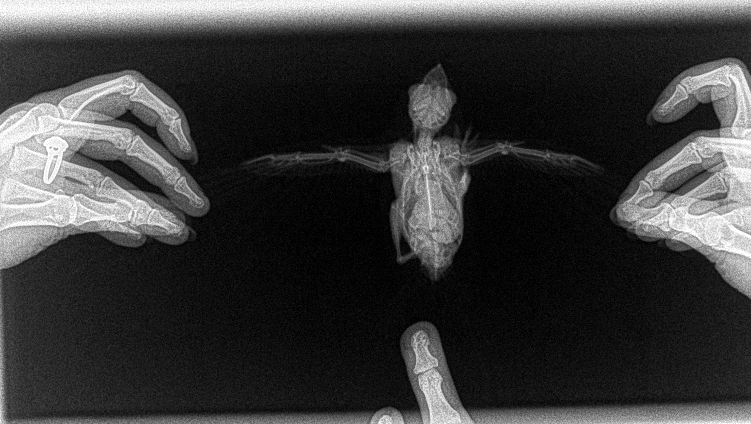

Добрый день! В воскресенье 21 июля  нашла  стрижа, сидел на земле. Состояние следующее -вес 44 грамма, корм - мороженые сверчки примерно 14-15 грамм в день. Зрачки сужаются симметрично, иногда держит один глаз закрытым. Держу в коробке, сейчас ведет себя достаточно активно - залезает на тряпку на стенке, шебуршит, но летать не может и когда падает на спину встать  самостоятельно не может, приходится переворачивать. Также вчера заметила кровь в ноздре однократно, сегодня засохшую кровь под клювом -источника кровотечения найти не получается, изначально крови не было. Из медикаментов -ноотропил ампульный, витамин в 1, мелоксикам. На что больше похоже -чмт, травма плечевого полиса? Прилагаю рентген и  видео, буду очень благодарна если кто-то посмотрит. Очень интересуют перспективы, хотелось бы выпустить хотя бы в середине августа, т.к. пмж животного не рассматриваю.

2019-07-24_171156.png